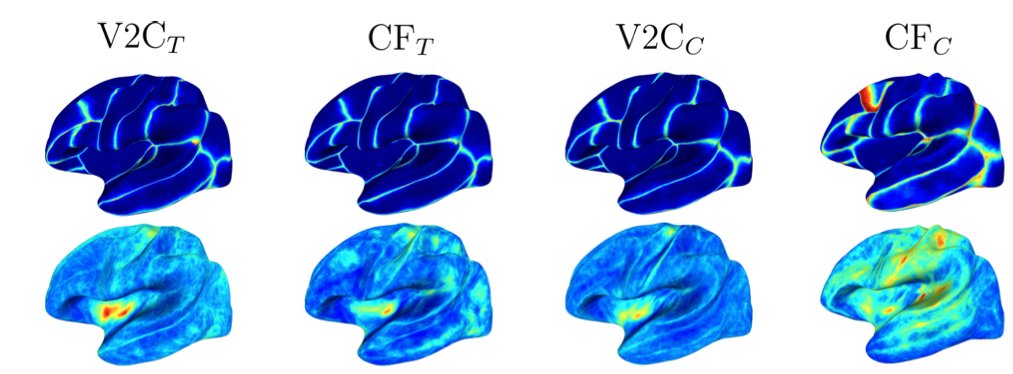

Deformation of a brain template to reconstruct the gray matter of a person's brain from an MRI scan. The video shows the integration of the ODE with the Euler method, learned by V2C-Flow. Code: github.com/ai-med/Vox2Cor… Article: authors.elsevier.com/c/1iVAd4rfPmHq… wonga et al TU München